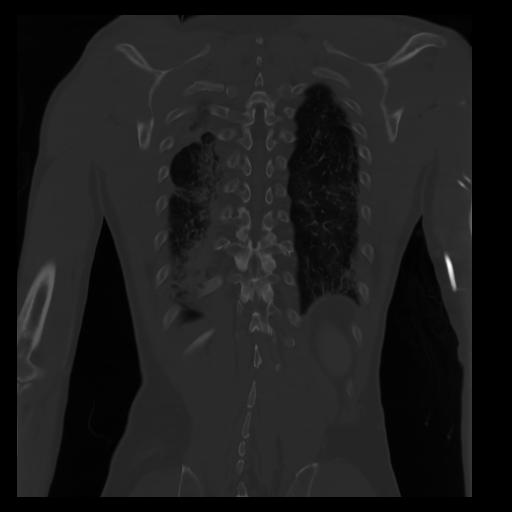

29 CUERPO,CE,Coronal,3.000,CUERPO,Coronal,